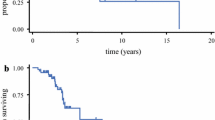

Recent investigations have demonstrating the importance of the volumetric estimation of EOR as predictor of survival [8, 159,160,161,162,163,164].

Robust retrospective analysis of prospective data from a randomized trial yielded level IIB evidence that the EOR, maximized by a different combination of intraoperative tools, is positively associated with the OS in GG4 patients [23, 67, 163, 166, 167, 170,171,172].

Traditionally gross total resection (GTR) of post-contrast T1-weighted MRI tumor has been shown to improve OS and progression free survival (PFS) in patients with newly diagnosed GBM compared to subtotal resection (STR) or biopsy in multiple large population studies [23, 166]. However, in recent years, an increasing number of studies have documented that any increase in EOR is correlated to higher OS and PFS. One of the first papers published by Lacroix on a series of patients with GBM showed that a macroscopic excision greater than 98% of the total lesion correlated with a prolonged survival up to 13 months [23], compared to 8 months in patients with lower EOR values [161].

In 2016, Brown et al. [43] published a systematic literature review on EOR studies conducted in adult patients with newly diagnosed supratentorial GBMs, including 37 studies, published over the last four decades, with suitable data for meta-analysis (41,117 patients) [43]. Volumetric evaluation of residual tumor was not used in most of them, thus patients were stratified according to the subjective categories “total removal” and “subtotal removal”. Patients who had a GTR, based on the absence of contrast-enhancement on post-op MRIs, had a 61% chance of survival at 1 year after surgery, which was reduced to 19% at 2 years, and were 51% more likely to be free from disease progression at 1 year than those undergoing STR.

In a later retrospective study, Sanai et al. demonstrated a stepwise improvement in OS over 95% (p < 0.0001) [174].

Although current literature strongly supports the role of EOR as independent predictor of OS, underling different survival benefit across the resective categories, recent studies evidenced that the absolute residual tumor volume might be prognostically more relevant than the proportion of removed tumor [37, 160, 169, 178].

A multicenter, randomized phase III study on fluorescence guided surgery (FGS) using 5-ALA showed a more complete resections of tumors in enhancing-glioma patients and better patient outcomes than with conventional microsurgery. Complete resection of the enhancing portion of newly diagnosed GG4 occurred in 65% of patients using 5-ALA versus 36% in those assigned to conventional surgery white light group (difference between groups 29% [95% CI 17–40], p < 0·0001). In addition to higher rate of complete resections, overall progression-free survival at 6 months (PFS-6) was also significantly greater with 5-ALA FGS (41.0% [32·8–49·2] vs. 21.1% [14·0–28·2]; p = 0.0003) [168].

In several studies, it has been shown that tumor resection carried out with the aid of 5-ALA fluorescence is associated with a greater rate of GTR and an increase in PFS [251, 254].

When a signal alteration is documented in follow-up MRI images post-adjuvant therapy, a differential diagnosis should be considered within progression and pseudoprogression. Multi-disciplinary discussion and advanced MRI images could define the real glioma recurrence [310, 311]. It remains unavoidable even if improvements in oncological and surgical treatments may delay this event. The indication to a second surgical operation for HGGs is controversial, in particular regarding selection of patients. In the literature, several variables have been considered to support surgical decision. Reoperation, especially when associated with a favourable preoperative Karnofsky Performance Status (KPS) at recurrence, was regarded as statistically significant variable for improved survival [90, 92, 312,313,314,315]. A greater EOR at 1st and 2nd surgery correlate with longer OS 88,89,90,91,92. Nevertheless, regarding surgical variables, conflicting results have been reported in the literature. Some authors found no significant effect of surgery on survival, or no difference between gross-total resection (GTR) and partial resection [316, 317]. However, there are growing evidences that EOR > 98% at second surgery greatly improve the OS [318, 319]. GTR at second surgery seem to correlate with better OS and post-operative KPS [88,89,90,91,92]. Finally, a benefit is reported in patients with higher KPS score at diagnosis, a greater EOR and initial diagnosis of WHO grade III. About one-third of patients with HGG may be eligible for salvage surgery at the time of progression [320].